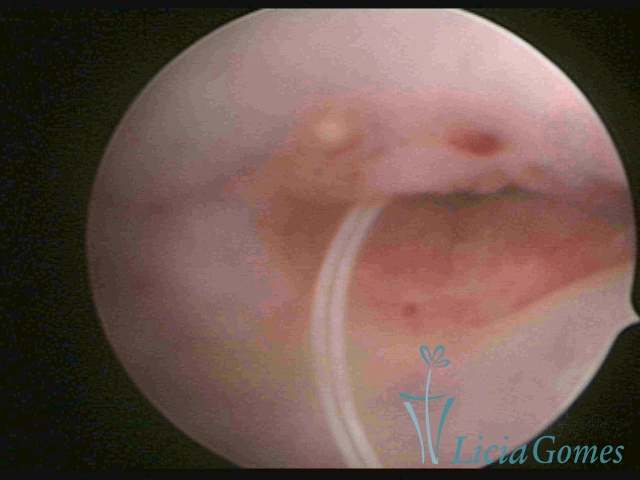

Cesarean section scar with a non-absorbed suture, as a foreign body